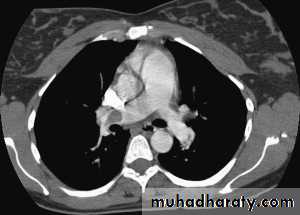

CT pulmonary angiography (CTPA)

It visualizes the distribution and extent of emboli in positive cases.

It may also prove alternative diagnosisSimultaneous visualization of femoral and popliteal veins for DVT improves sensitivity.

Can be performed safely in pregnant women (with foetal shielding).